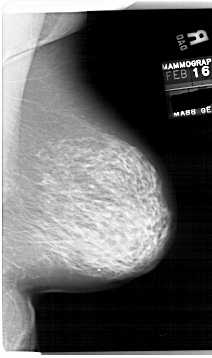

A_1854_1.RIGHT_MLO

RIGHT_MLO LINES 6796 PIXELS_PER_LINE 4021 BITS_PER_PIXEL 12 RESOLUTION 43.5 NON_OVERLAY